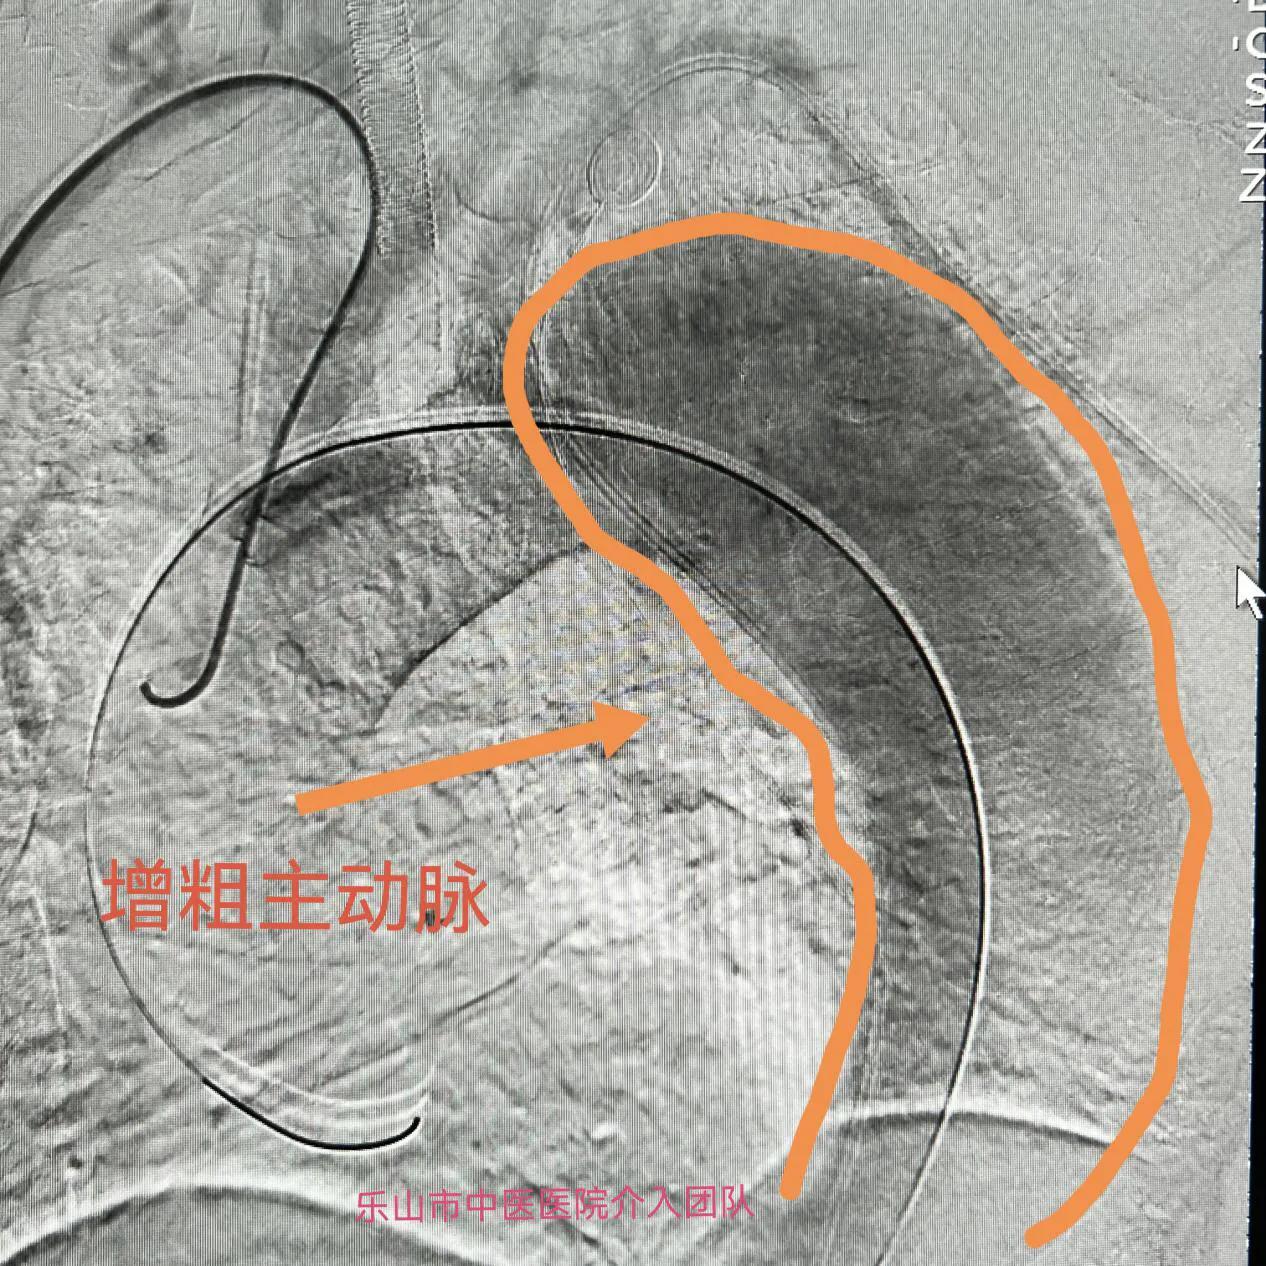

入院后查体,头颅磁共振检查发现右椎动脉夹层动脉瘤;同时,胸腹部增强CT及血管成像提示主动脉夹层(Stanford B型),腹腔干、左肾动脉由假腔供血,肠系膜上动脉由真假腔供血。

考虑到病人病情复杂,介入科团队决定分次进行手术,“先处理椎动脉夹层动脉瘤,待术后平稳后再行二期手术处理主动脉夹层动脉瘤”。10月15日,经周密术前准备,科室副主任刘先军带领医生团队,为患者成功行椎动脉血流导向装置pipeline置入,五天后再行分支型主动脉腹膜支架置入。术中各项指标稳定,目前患者已逐步康复。